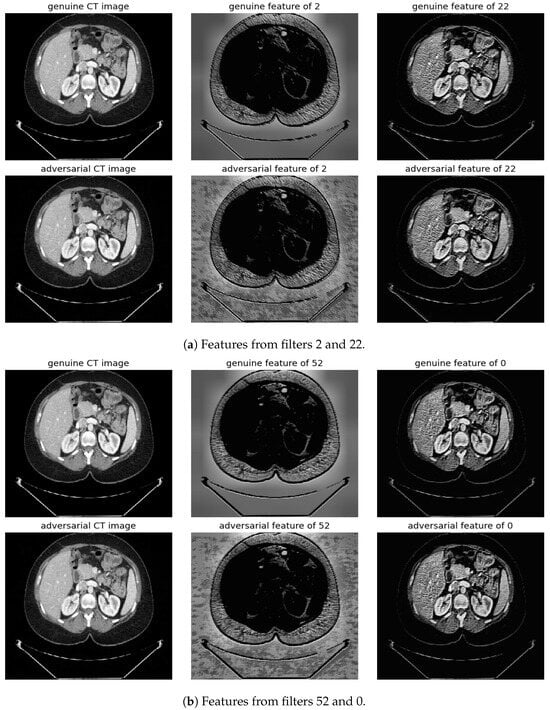

Randomly selected genuine CT samples, alongside their adversarial versions, are displayed in Figure 9, Figure 10 and Figure 11. The adversarial samples were generated using FGSM, BIM, and SMIA attack methods, each with an epsilon of 0.01. While BIM and SMIA used 5 iterations, FGSM did not. These samples represent the most challenging scenarios for human visual detection. Despite the modest epsilon value, as indicated in Table 3, the adversarial attacks have a subtle but pronounced effect. Such slight modifications can lead to major diagnostic inaccuracies potentially impacting patient care.

Figure 9.

Visualization under FGSM Attack: Comparison of features from the first layer between genuine and adversarial samples for the most sensitive (filters 2 and 52) and least sensitive (filters 22 and 0) filters.

To address this, histogram equalization as feature post-processing is applied. The visual representations underscore that while genuine and adversarial samples might appear similar to the naked eye, post-processing brings forth distinct feature differences when employing the most sensitive filters from 2 and 52. Perturbations, especially noticeable in the background of the adversarial samples, are frequently highlighted by these filters. Conversely, features processed with filters from 22 and 0, deemed less sensitive in prior analyses, fail to offer a stark visual contrast.